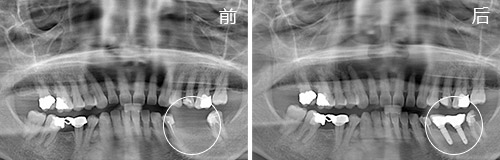

年龄:62岁

因为刷牙比较马虎,口腔清洁不力造成多颗牙齿蛀牙,部分做了补牙和固定修复,左下颌的磨牙由于没能及时修复而缺失。佩戴活动假牙一天之内要反反复复掉好几次,无法畅快吃一顿饭。

种植情况:种植2颗

种牙时间:2014年11月(已种牙1年9个月)